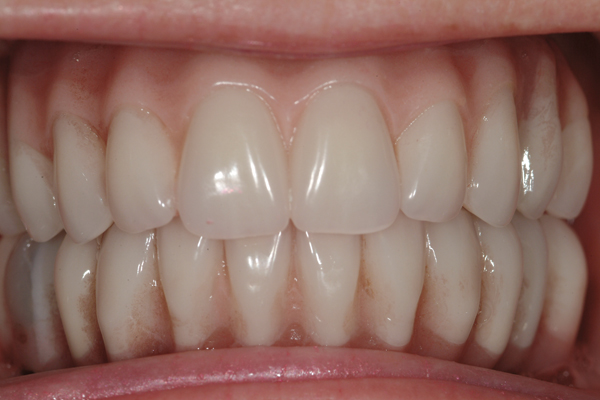

Fig 17. Pre-treatment smile of patient with terminal dentition.

Figure 17

Fig 18. The patient’s intraoral condition.

Figure 18

Fig 19. Patient smile shown 3 years post-treatment.

Figure 19

Fig 20. Patient intraoral condition 3 years following delivery of maxillary and mandibular All-on-4 definitive prosthesis.

Figure 20

Dental rehabilitation with the All-on-4 treatment concept is often a life-changing event for edentulous and terminal dentition patients that results in unprecedented quality of life improvements (Figure 17 through Figure 20).